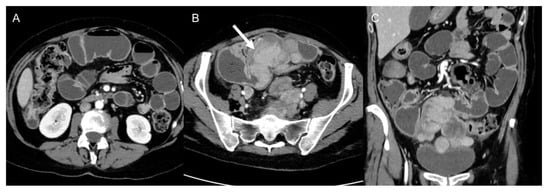

5. Complications

Complications are usually related to tumor invasion of adjacent structures or to mass effect caused by the tumor and include hydronephrosis, pulmonary embolisms secondary to compression of inferior cava vein, nerve compression, bowel obstruction (Figure 11) [49], and even intestinal perforation [50]. Postoperative complications are divided into early and late complications and include pulmonary embolism, ileus, fluid collections, hemorrhage [49], splenic injuries, sepsis, multisystem organ failure. For these reasons, guidelines recommend that immediate postsurgical care should be held in subspecialized facilities [2,19,51,52,53].

Figure 11.

Bowel obstruction in 38-year-old woman with metastatic leiomyosarcoma. Axial (A,B) and coronal (C) CT images on the venous phase show dilatation of small bowel loops with air–fluid levels secondary to the presence of metastatic masses (arrow) in the pelvis.